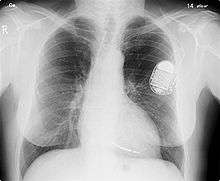

Permanent pacing with an implantable pacemaker involves transvenous placement of one or more pacing electrodes within a chamber, or chambers, of the heart, while the pacemaker is implanted inside the skin under the clavicle. The procedure is performed by incision of a suitable vein into which the electrode lead is inserted and passed along the vein, through the valve of the heart, until positioned in the chamber. The procedure is facilitated by fluoroscopy which enables the physician to view the passage of the electrode lead. After satisfactory lodgement of the electrode is confirmed, the opposite end of the electrode lead is connected to the pacemaker generator.

The pacemaker generator is a hermetically sealed device containing a power source, usually a lithium battery, a sensing amplifier which processes the electrical manifestation of naturally occurring heart beats as sensed by the heart electrodes, the computer logic for the pacemaker and the output circuitry which delivers the pacing impulse to the electrodes.

Most commonly, the generator is placed below the subcutaneous fat of the chest wall, above the muscles and bones of the chest. However, the placement may vary on a case by case basis.

The outer casing of pacemakers is so designed that it will rarely be rejected by the body's immune system. It is usually made of titanium, which is inert in the body.